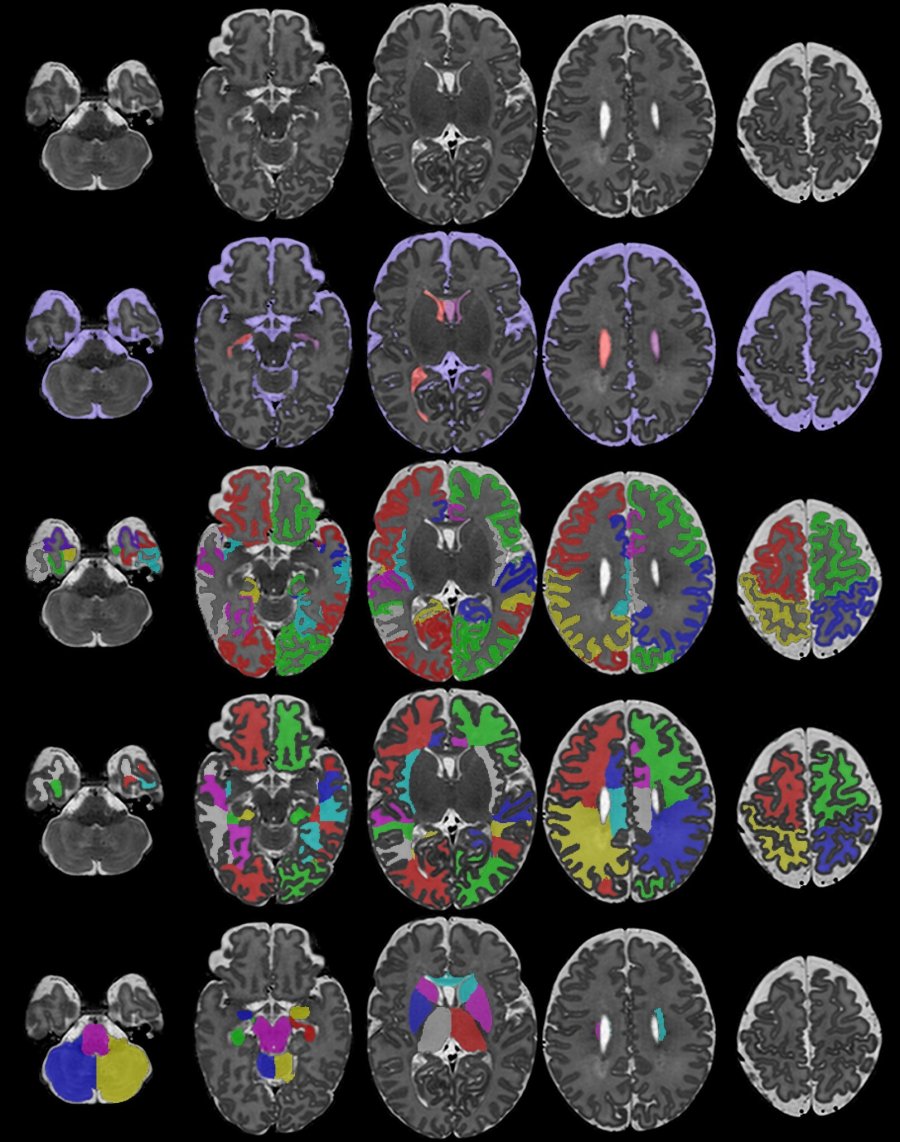

La nueva investigación utilizó una prueba avanzada de imágenes llamada tomografía por emisión de positrones (TEP) y examinó a 31 personas con fibromialgia y 27 «controles» sanos de Boston y Estocolmo, Suecia.

Cuando los investigadores compararon las exploraciones de personas con fibromialgia con controles sanos, vieron más inflamación en las células inmunitarias del cerebro (glia) en personas con fibromialgia.